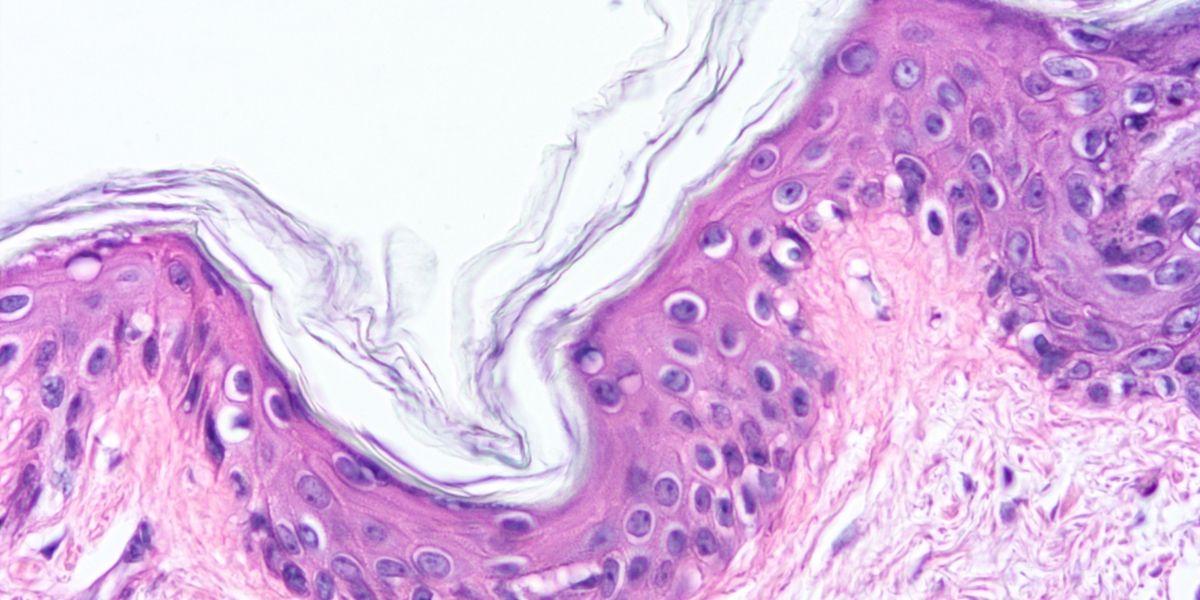

A bone marrow biopsy can be performed for diagnosis, which, together with the analysis, will allow the determination of risk factors for the progression of the disease, which will guide treatment.